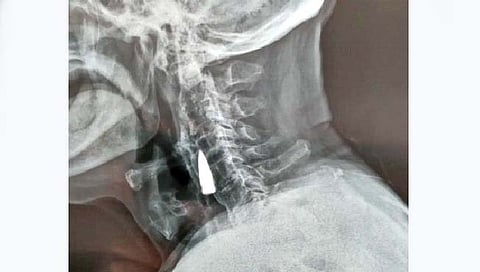

तब्बल 77 वर्षांपासून मानेत बंदुकीची गोळी!

चीनमधील 95 वर्षांचे झाओ एक निवृत्त सैनिक आहे. शँनडाँगमधील एका रुग्णालयात ते गेले. तिथे त्यांच्या मानेचा एक्स-रे काढण्यात आला. जो पाहून डॉक्टर हादरले. कारण त्यांच्या मानेत बंदुकीची गोळी अडकली होती. मानेत बंदुकीची बुलेट म्हणजे मृत्यूच म्हणावा लागेल. त्यांनाही त्यांच्या मानेत गोळी अडकल्याचे पहिल्यांदाच समजले.

दुसर्या महायुद्धावेळी त्यांना ही गोळी लागली होती. याला जवळपास 77 वर्षे उलटली आहेत. झाओ यांचे जावई वांग यांनी सांगितलं की, युद्धावेळी त्यांना अनेक वेळा गोळ्या लागल्या होत्या; पण त्यांच्या मानेतही गोळी लागली होती याची त्यांनाच माहिती नव्हती. डॉक्टर म्हणाले, गेल्या 77 वर्षांपासून त्यांच्या मानेत ही गोळी अडकली आहे; पण झाओ यांना यामुळे कधीच समस्या झाली नाही हे चमत्कारिक आहे. पण आता माहिती झाल्यानंतरसुद्धा त्यांच्य मानेतील ही गोळी आपण काढू शकत नाही याचं कारण म्हणजे झाओ यांचं वय. त्यांचं वय खूप आहे आणि जर आता त्यांच्या मानेचं ऑपरेशन करून गोळी काढण्याचा प्रयत्न केला तर त्यांच्या जीवाला धोका आहे.